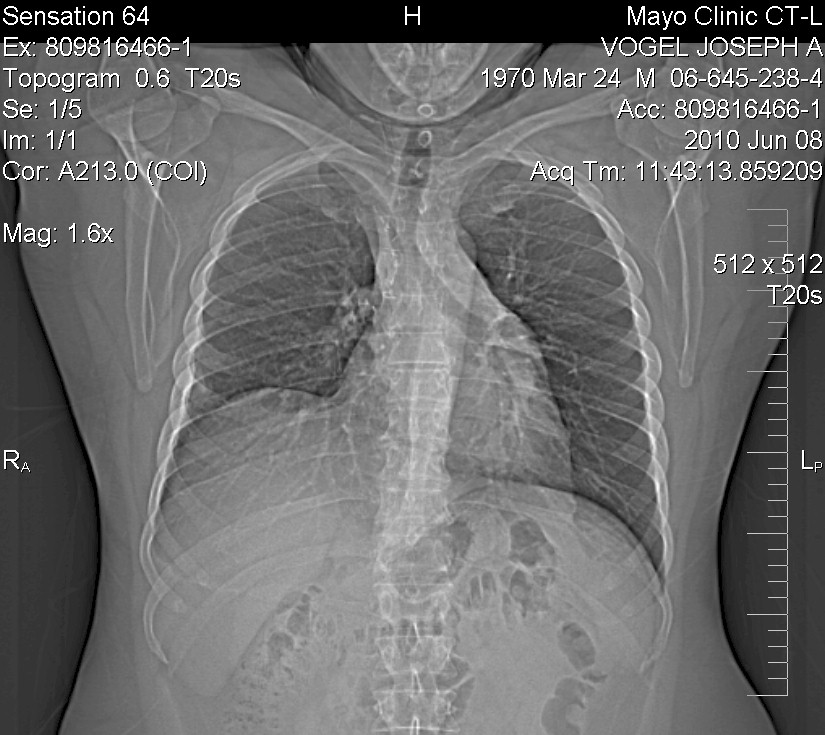

X-Ray of my chest done by Mayo and indicated as

"abnormal lung" in October 2009:

So, as you can see, basically the EXACT same!

Which in one way was good since it had not gotten worse, BUT it was the exact

same so Solantic totally missed it!

Arg!

So, as of December 2009, with the upper right lobe of the lung removed, my

current chest x-ray looks like:

As time passes, they say the two remaining lobes might grow in size to since

there is more room, but the doctors say all looks great as of that date.

X-ray on follow-up after surgery/recovery - December 15 2009

CT Scan - 6 months later - June 25th 2010 - Based on

the notes from the scan, all appears good (aka "unremarkable")